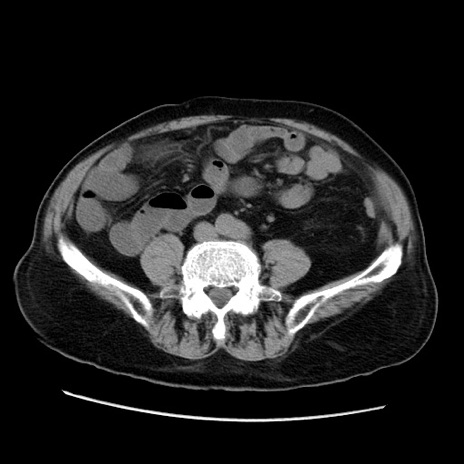

症例21(横断像)

【症例】70歳代男性

【主訴】腹痛

【現病歴】肝硬変・肝細胞癌にてかかりつけの方。約9時間前に食後より腹痛出現。症状が徐々に増悪し、嘔吐出現したため来院。

【既往歴】肝硬変、肝細胞癌(RFA、TACE後)

【身体所見】意識清明、表情苦悶様、BT 36℃、BP 129/78mmHg、P 88bpm、SpO2 97%(RA)、右上腹部から心窩部にかけて圧痛あり、反跳痛なし、筋性防御あり。

【データ】WBC 5800、CRP 0.16